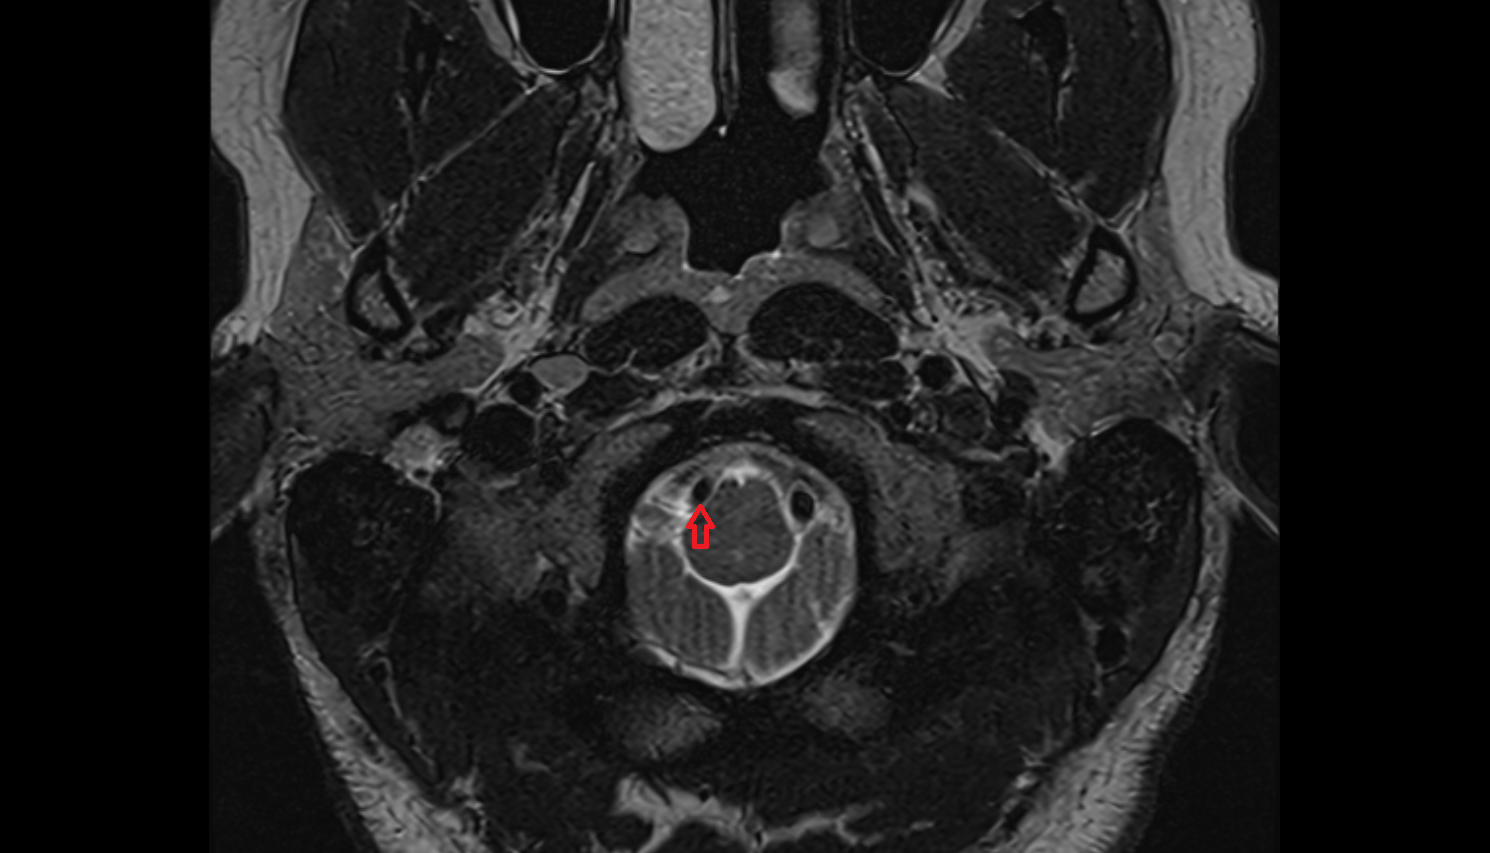

- Spinal cord

- Upper cervical spinal cord